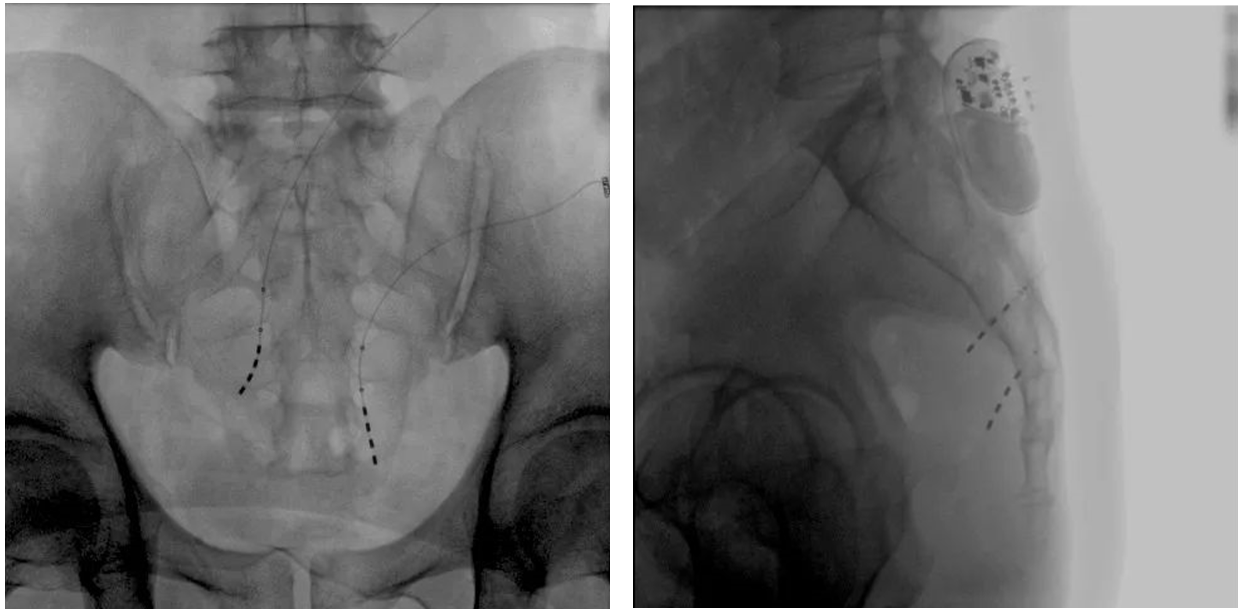

大平板一體式移動C形臂術(shù)中影像

在骶神經(jīng)調(diào)控術(shù)或者骶神經(jīng)刺激術(shù)(SNS)中,醫(yī)師首先會在透視引導(dǎo)下把電極通過導(dǎo)針插入到骶3神經(jīng)孔位置,通過脈沖電流的刺激,達到興奮神經(jīng)纖維并抑制逼尿肌收縮。在這一步,醫(yī)師會先對患者的神經(jīng)刺激反應(yīng)做測試評估,如果刺激效果明顯,說明該方案能夠達到手術(shù)預(yù)期。接下來醫(yī)師會在附近皮下脂肪處植入一塊脈沖電流發(fā)生器并與電極相連,使該部位今后能得到長期的電刺激,改善OAB癥狀。

? 傳統(tǒng)9英寸的平板探測器或影像增強器C形臂,成像范圍較小,在進行導(dǎo)絲定位觀察時,受手術(shù)床的限制無法呈現(xiàn)大視野的透視圖像,需要進行多次的拍攝,降低手術(shù)的效率。而普愛醫(yī)療大平板一體式移動C形臂裝備一塊30cm x 30cm大平板探測器,超大的成像區(qū)域彌補了因擺位不便造成的拍攝困難。

? 相較于影增C形臂,平板探測器成像的畸變更少,能夠準確體現(xiàn)電極和骶孔位置關(guān)系,提高手術(shù)效果預(yù)期。